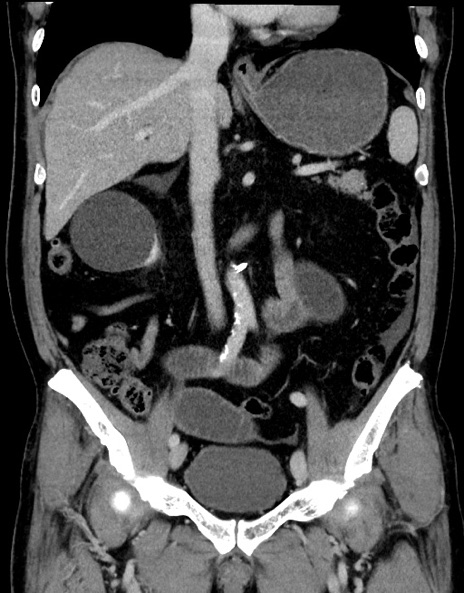

症例15(冠状断像)

【症例】70歳代男性

【主訴】腹痛

【現病歴】今朝から腹痛あり。全体的に痛い。特に左上の方。排ガスが今日はない。冷や汗が出る。

【既往歴】直腸癌術後

【身体所見】左側腹部〜上腹部に圧痛あり。腹膜刺激症状明らかなではない。軽度反跳痛。左下腹部に術後瘢痕あり。

【データ】WBC 7700、CRP 0.02

横断像